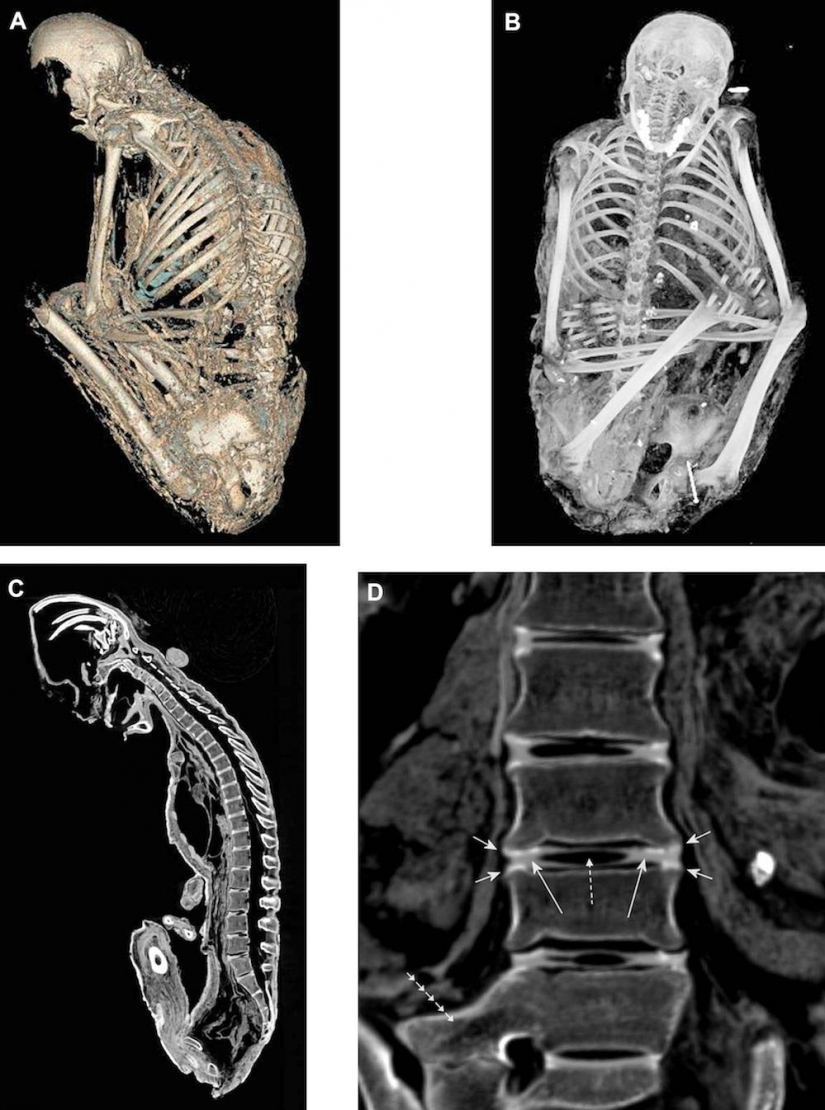

5. Los rayos X del cerebro, de 6 años, niña mostró que ella fue golpeada por un rayo. Aquí se muestra que las órbitas de los ojos, los nervios ópticos (flechas) y la óptica de los músculos.

6. X-ray de el cerebro de un 15-year-old girl muestra que entre la blanca y la materia gris del cerebro hay una división. Las flechas señalan el aire que rodea el cerebro.

7. Y que los rayos x mostraron que el cerebro de 5 años niño se quedó en perfecto estado.

17. Los rayos X del cuerpo del Inca momias.